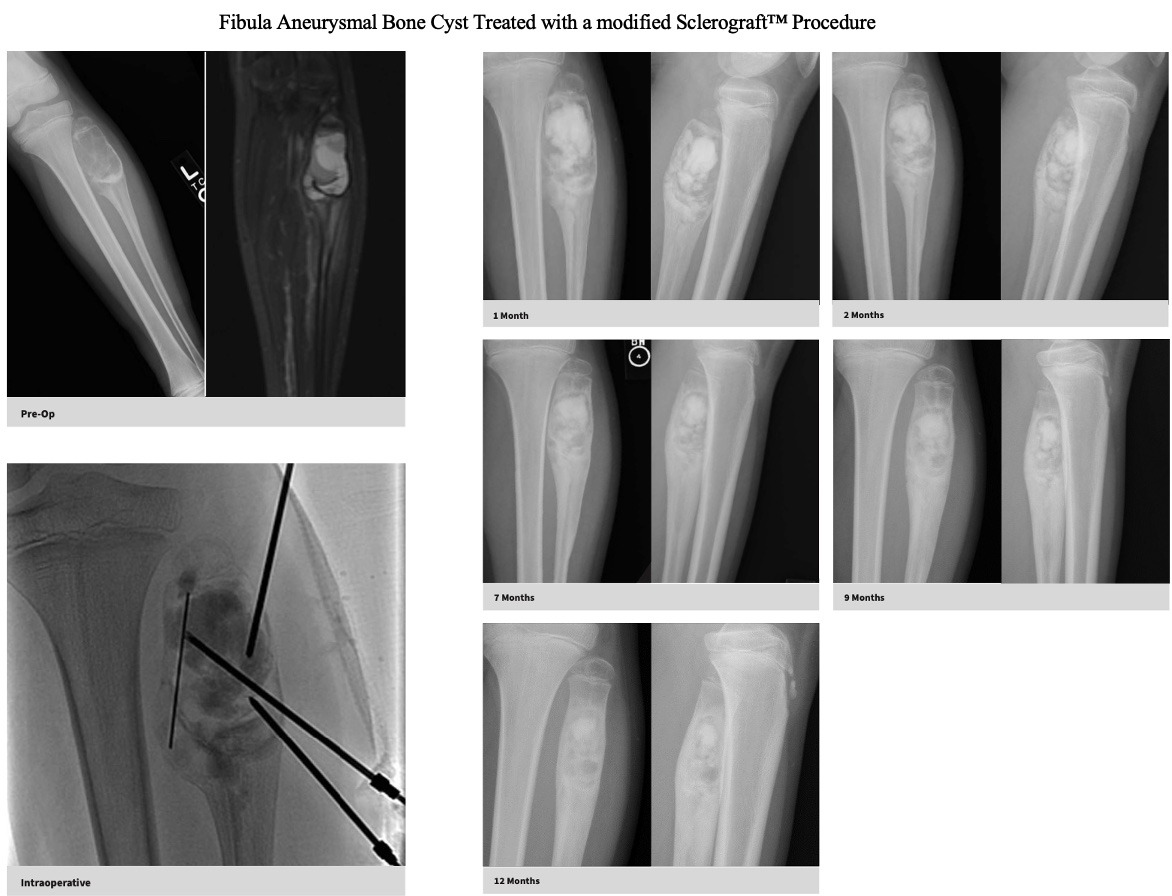

Utilizing needles, chemical sclerosis destroys the cyst wall and regenerative bone graft is injected via the needles to expedite bone healing.

The doctor uses imaging guidance (like X-ray or ultrasound) to guide needles into the cyst.

Chemical sclerosis using chemicals like doxycycline are washed through the cyst to kill the cyst wall lining

Regenerative bone graft is then injected through the needles and the needles are removed. The bone graft is temporary and is eventually reabsorbed by the body.

Quick recovery and bone formation seen between 6 weeks to 3 months

Proven success in both UBCs and ABCs

Gallery

Explore our educational resources and images